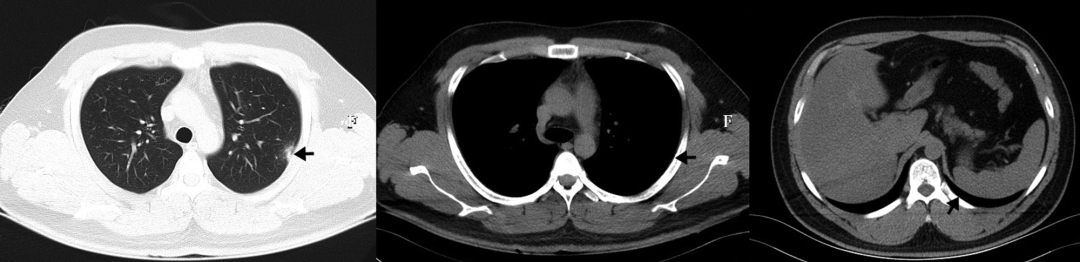

• 胸部CT显示左上肺有一个厚壁空洞,可见血管集束征和局部胸膜增厚(如图1所示)

图1:治疗前胸部CT显示左上肺厚壁空洞,内缘光滑,外缘不规则,邻近胸膜和左下胸膜增厚